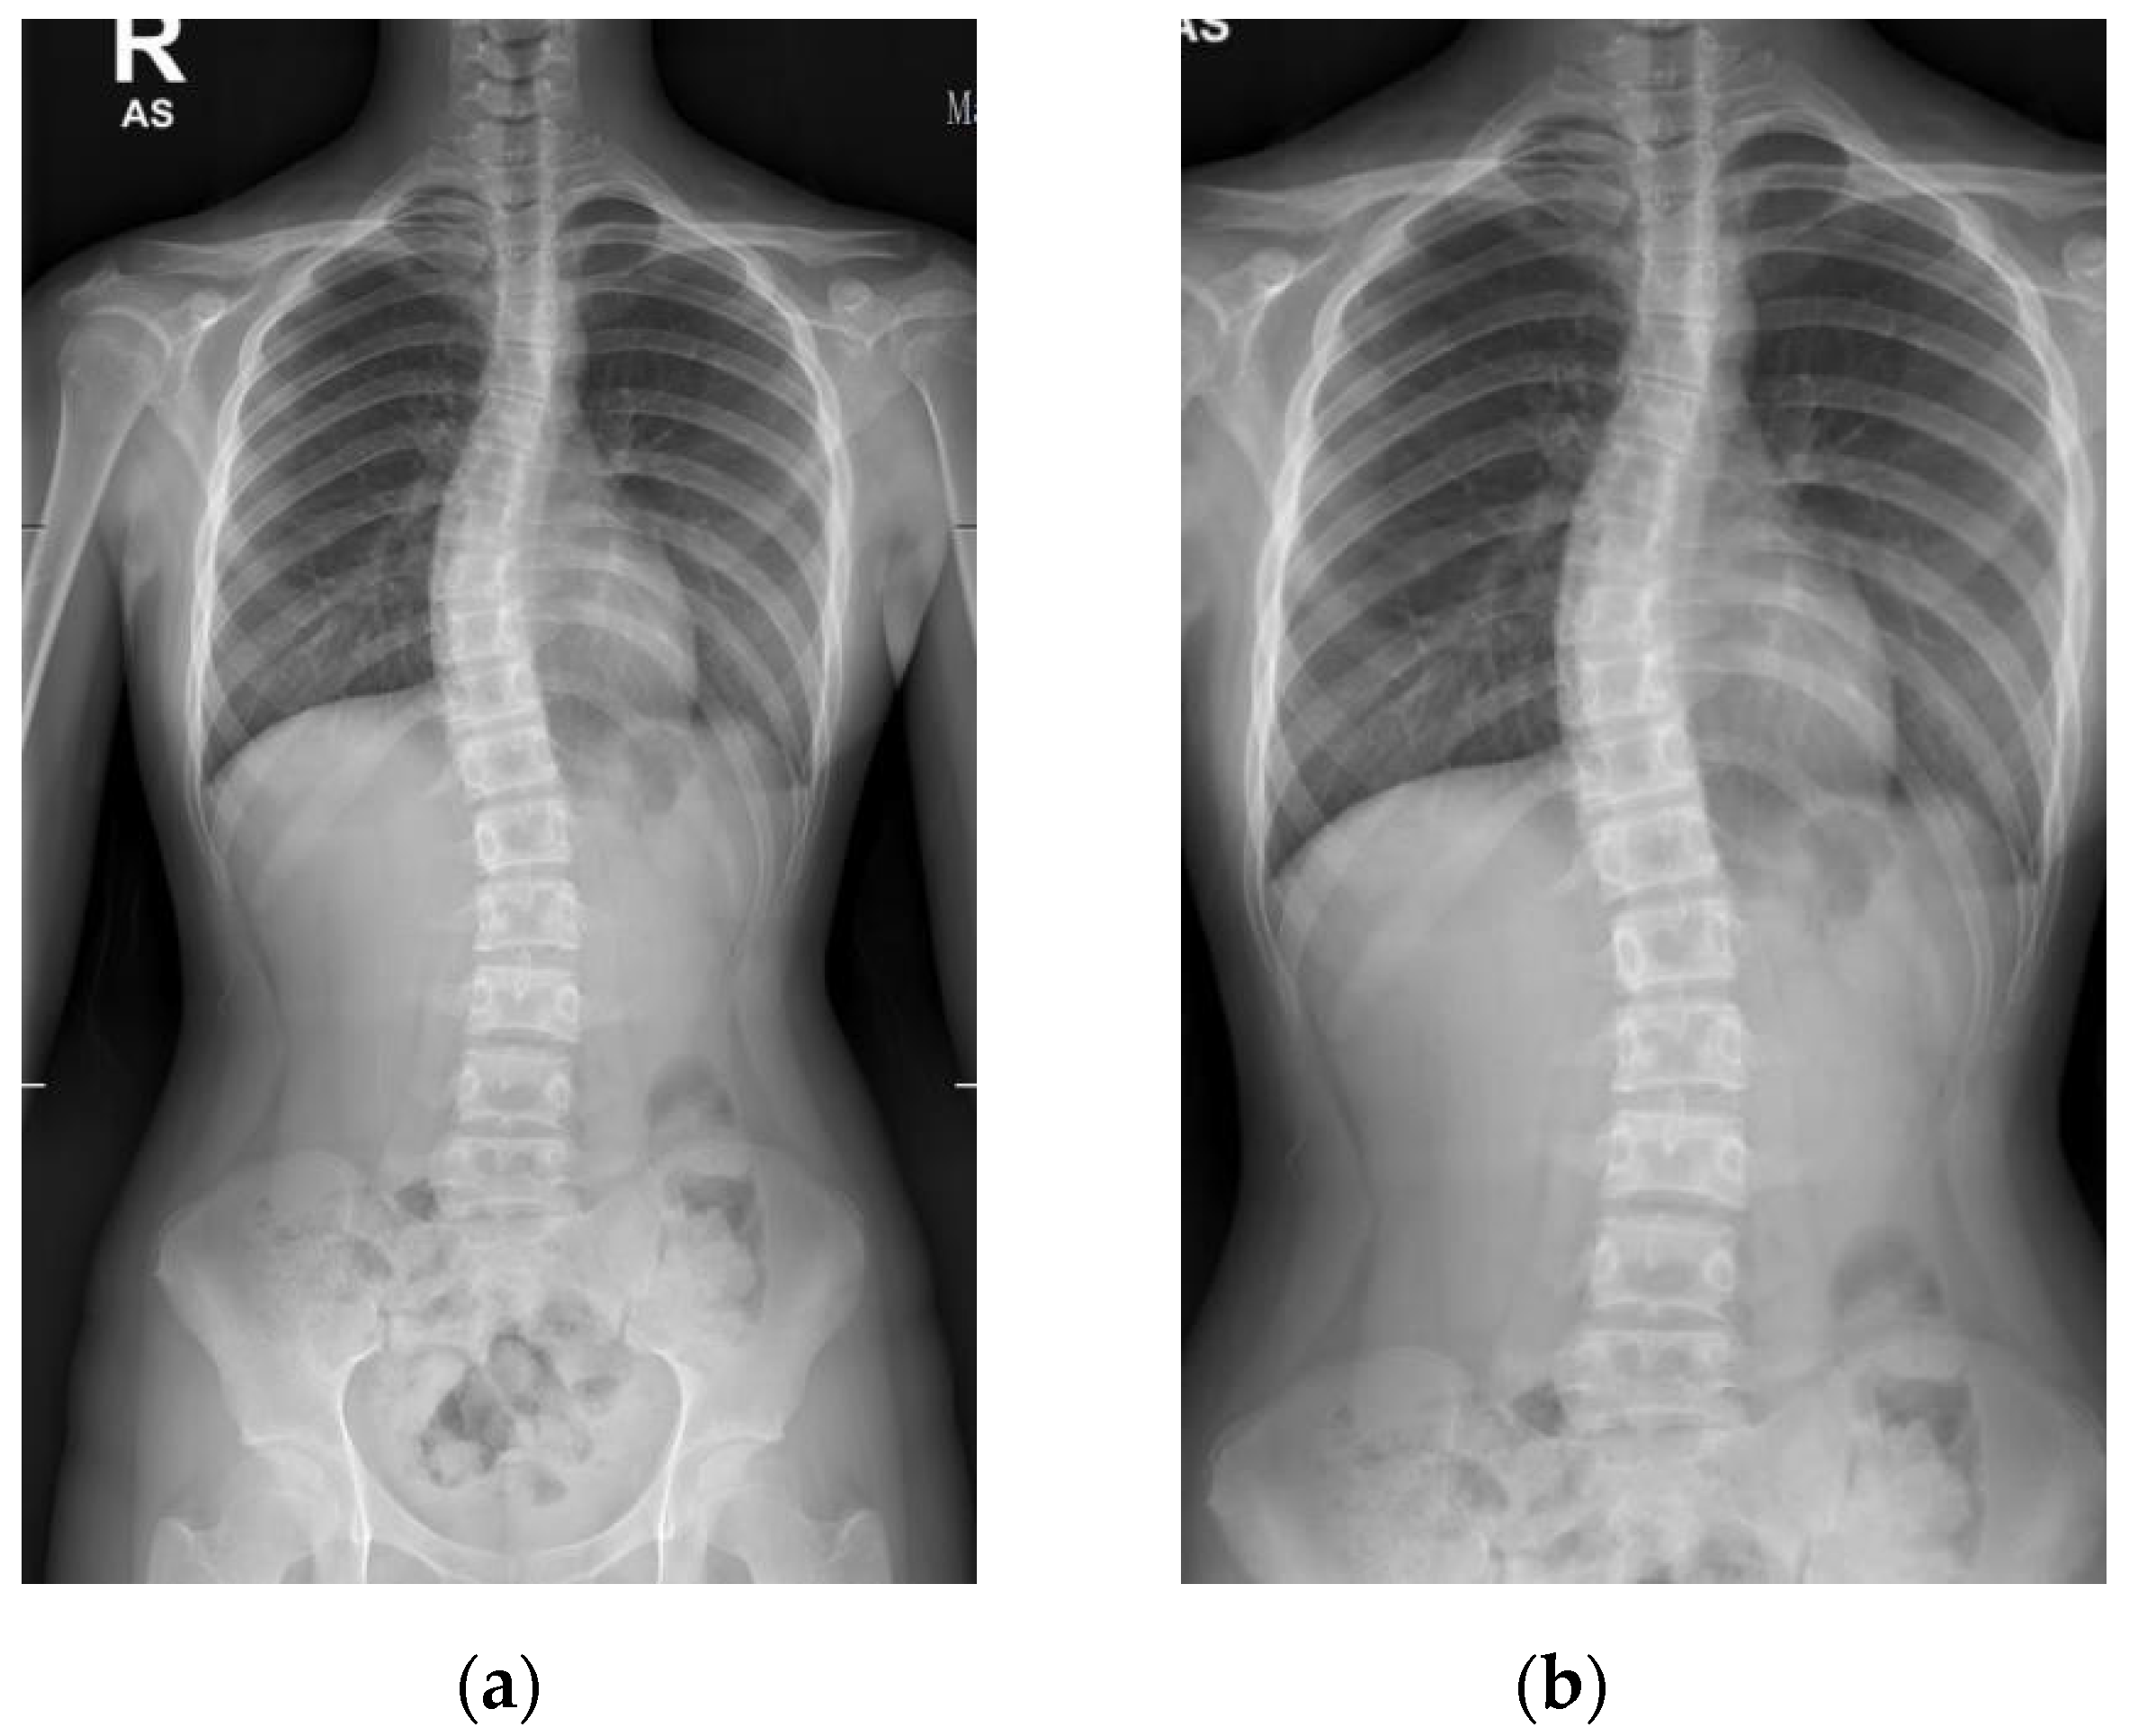

The collection and labeling of spinal images were performed by the public AASCE MICCAI 2019 anterior-posterior X-ray images dataset [18]. The input images vary in size from 359 × 973 to 1427 × 3755. Some challenging images can be handled due to our large number of training image conditions, which include images with different noise, contrast, lighting conditions, and spines with high CA, as shown in Figure 1. Each image contains 17 vertebrae from the thoracic (upper spine) and lumbar (lower spine) regions. The image input resolution is set to 1024 × 512 for the algorithm development. Each vertebra is located by four corner landmarks. The ground-truth of the 68 landmarks or points in each image is provided by the dataset.

Figure 1.

Examples of some challenging image conditions: (a) Image with noise; (b) high contrast image; (c) low light image; (d) spine with high CA.